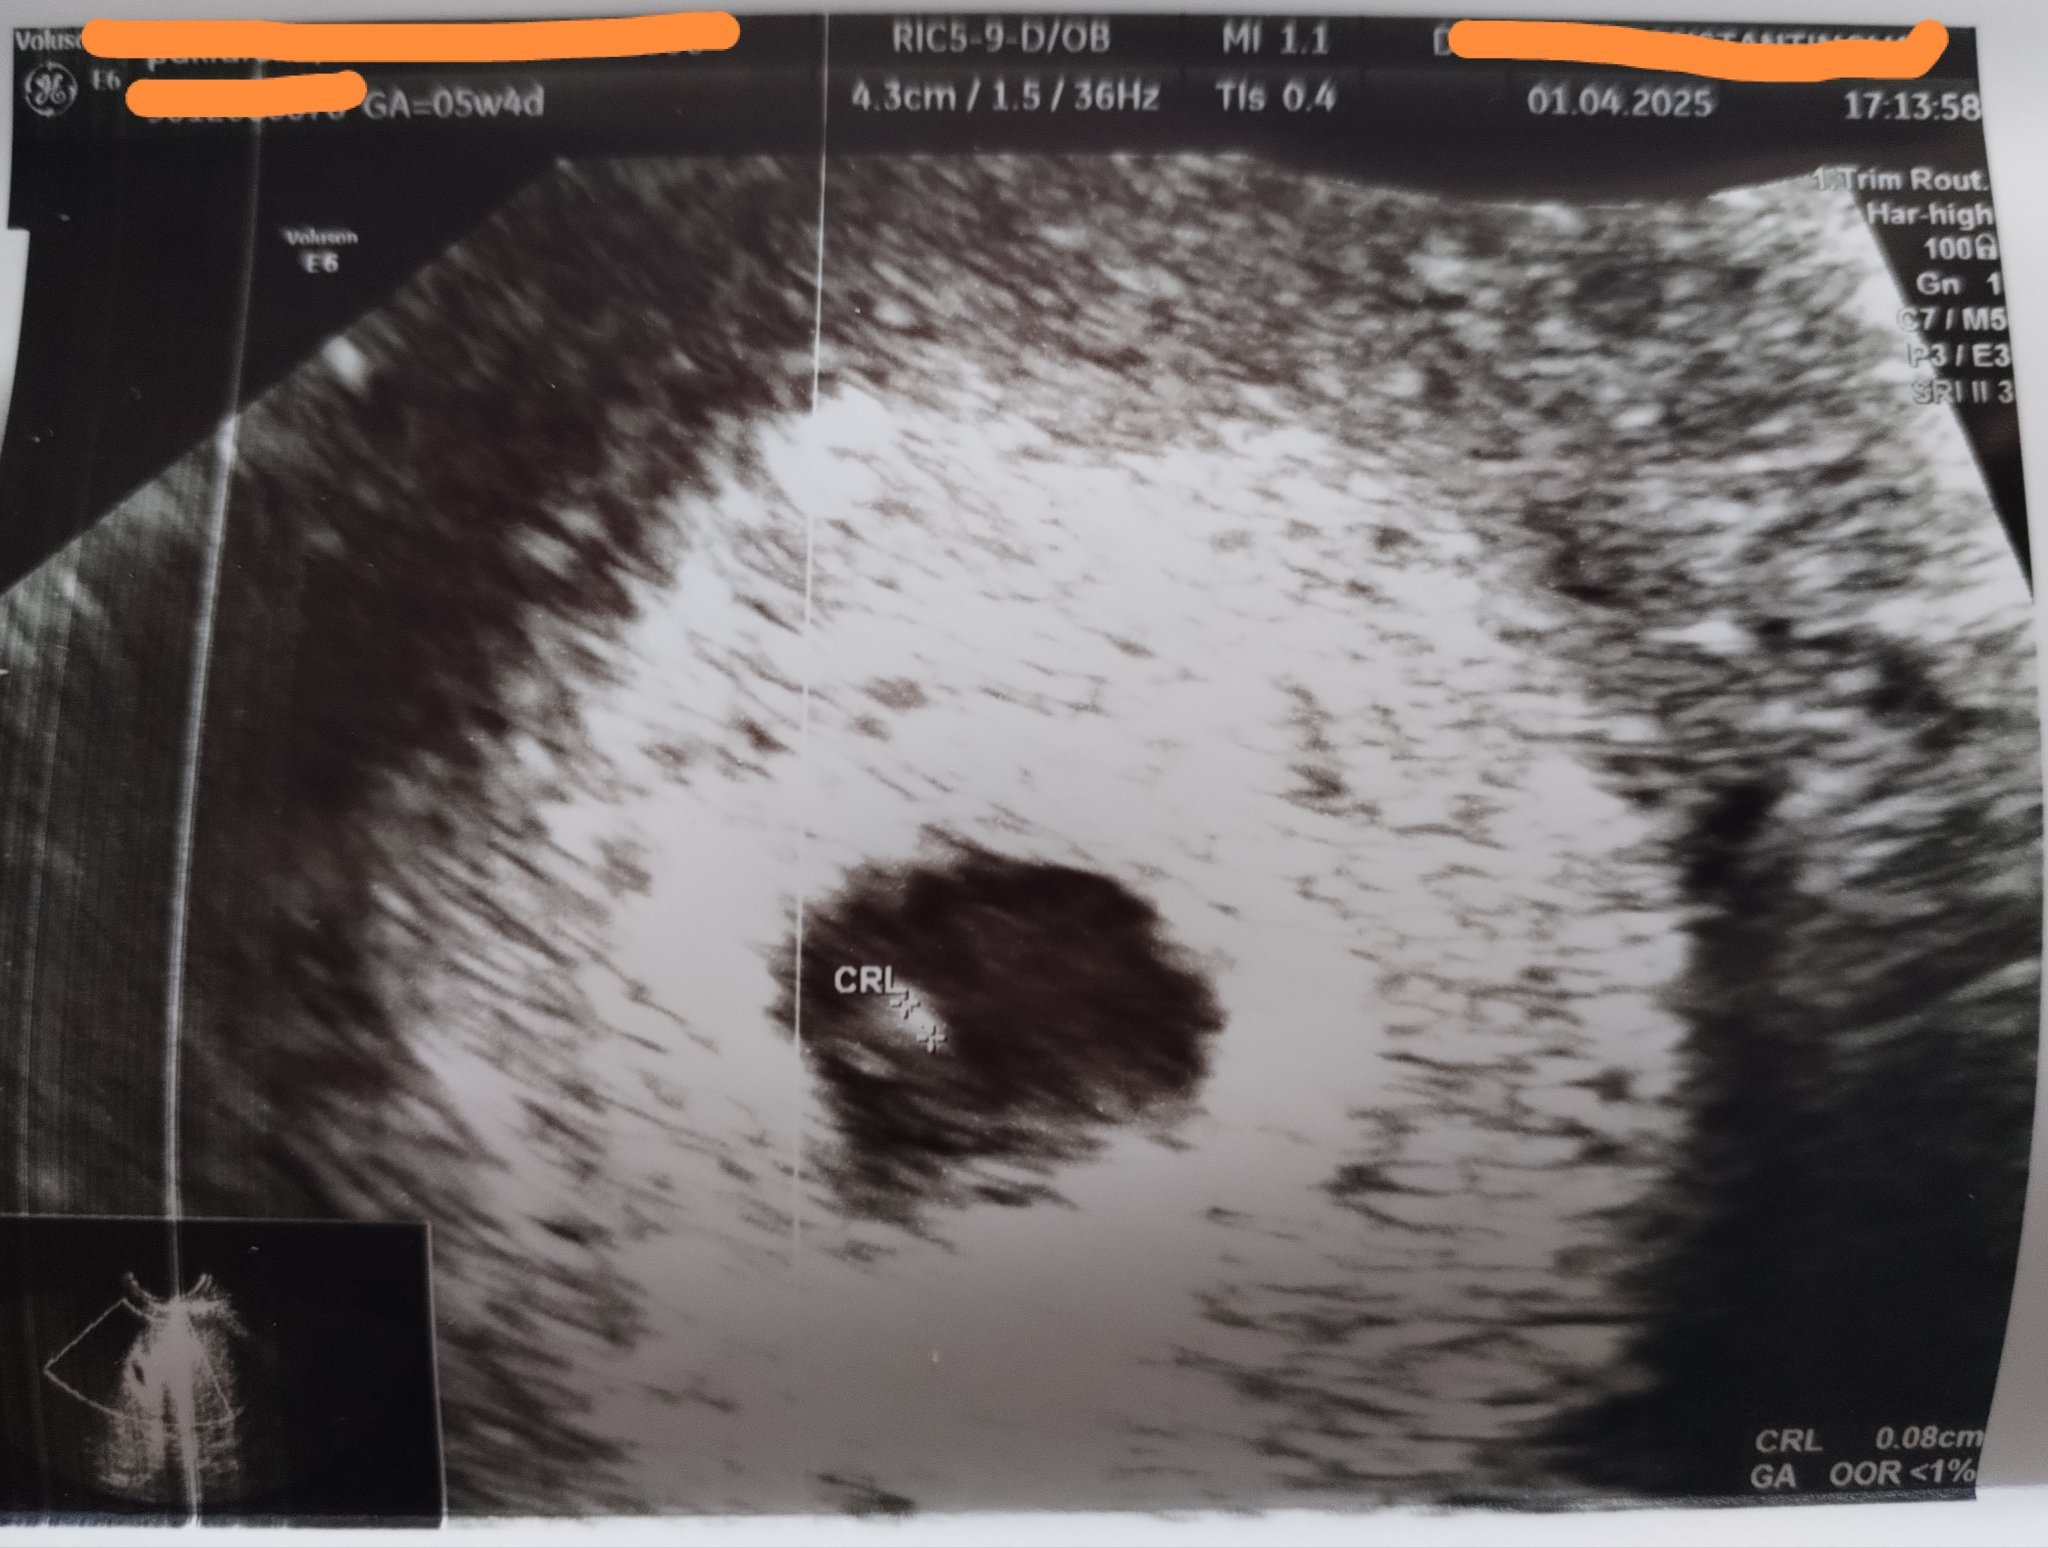

Според вас дали големината на ембриона , е добре за седмицата в която съм? Чухме и пулс. Доктора каза честито, но и накрая на прегледа каза на следващия преглед ще видим дали се развива, което малко ме притесни. Благодаря!

MilenaDA,всичко изглежда нормално.

Чухме пулс.

MilenaDA, не виждам нищо притеснително. Най-вероятно лекарят го е казал, защото чисто статистически 1 от 3 бременности приключва с аборт в ранните седмици. Щом не е изказал някакви конкретни притеснения относно твоята бременност, не виждам смисъл да разсъждаваш повече по въпроса. Изчакай си следващия преглед, а ако толкова чак се притесняваш - просто отиди при друг лекар за второ мнение.